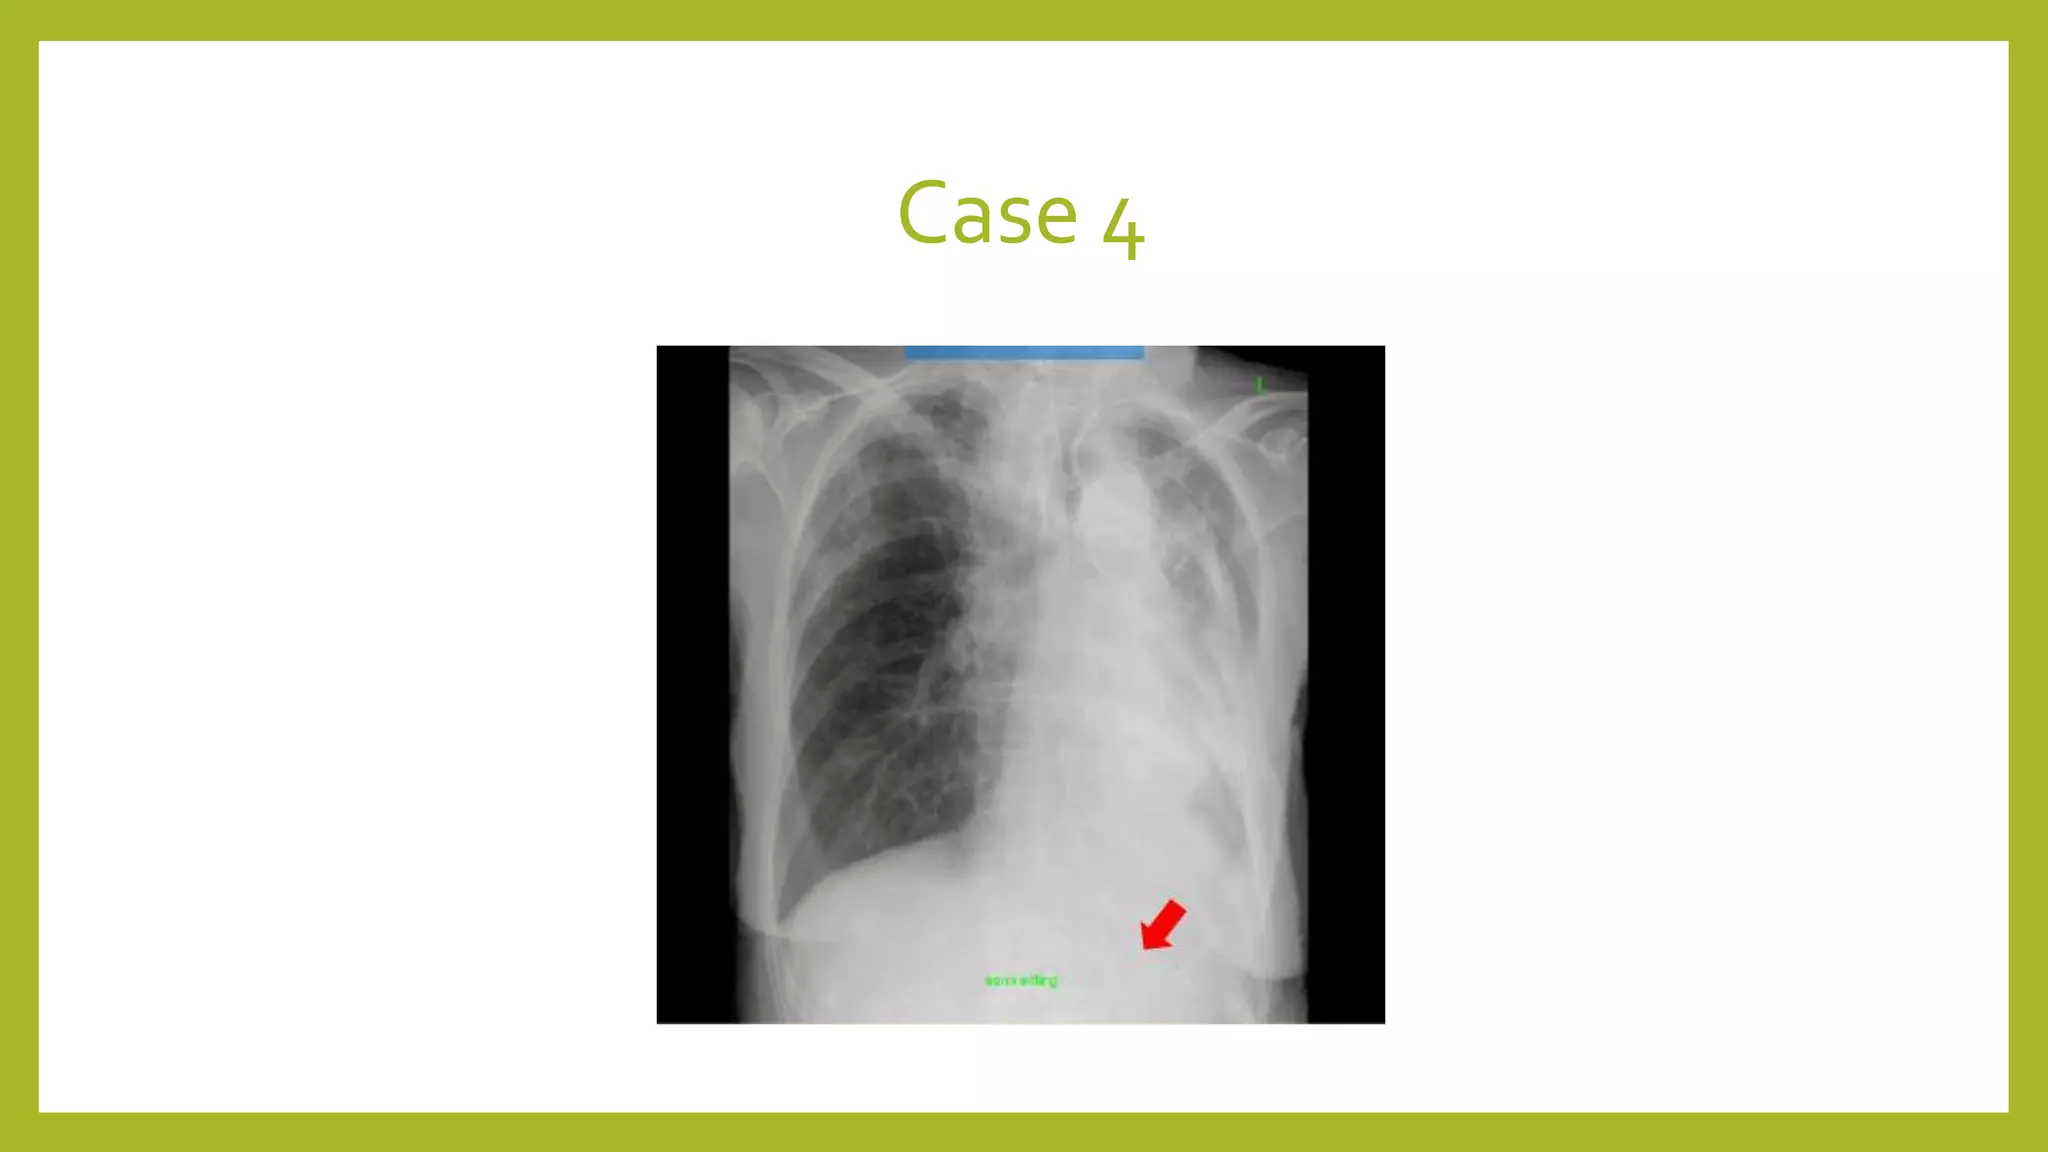

The document provides guidance on approaching and interpreting chest x-rays (CXR). It outlines steps to check the name, date and quality of the film, systematically scan the CXR looking for abnormalities, and determine if the lungs appear too white or black. Specific signs are described to help localize abnormalities, including the cardiac silhouette sign and pleural effusion signs. Examples are given of respiratory distress syndrome, tetralogy of fallot, transposition of great arteries, and total anomalous pulmonary venous return. The take home message is to summarize positive findings, compare to prior CXRs if available, and confirm findings with a radiologist.